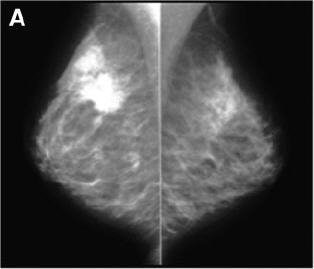

| Above, x-ray mammogram, profile views. Polycystic dysplasia of both breasts. On left, suspicious lesion in supra-areolar region of right breast, corresponding to ductal carcinoma on FNA. On right, left breast is dense, especially in superoexternal part of gland. Multiple cysts are seen with ultrasound but no suggestive lesion was evident. |